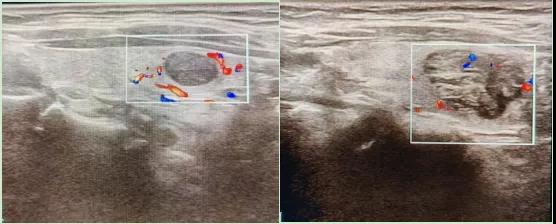

二、彩超如何“揪出”甲狀腺瘤?

彩超是一種無創(chuàng)、無輻射的檢查手段,被譽為甲狀腺的“高清攝像頭”。它的原理是:

超聲波探測:通過發(fā)射高頻聲波,生成甲狀腺的實時圖像。

彩色血流顯示:用紅藍色標記血流信號,區(qū)分腫瘤的供血情況。

醫(yī)生會通過以下特征判斷腫瘤性質(zhì):

1.形態(tài):良性多呈圓形,邊界清晰;惡性可能不規(guī)則、邊緣模糊。

2.回聲:低回聲結(jié)節(jié)風險較高(像“烏云”一樣暗)。

3.鈣化:細小砂礫樣鈣化提示惡性可能。

4.血流信號:惡性結(jié)節(jié)常有豐富紊亂的血流。